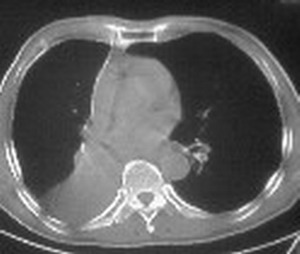

1:右侧结核性胸膜炎,胸腔积液;

2:不排除右肺癌。

影像特征很象,包裹性胸腔积液,建议楼主测ct值鉴别.

ct值12,包裹性胸腔积液,

右肺下叶未发育,并包裹性胸腔积液